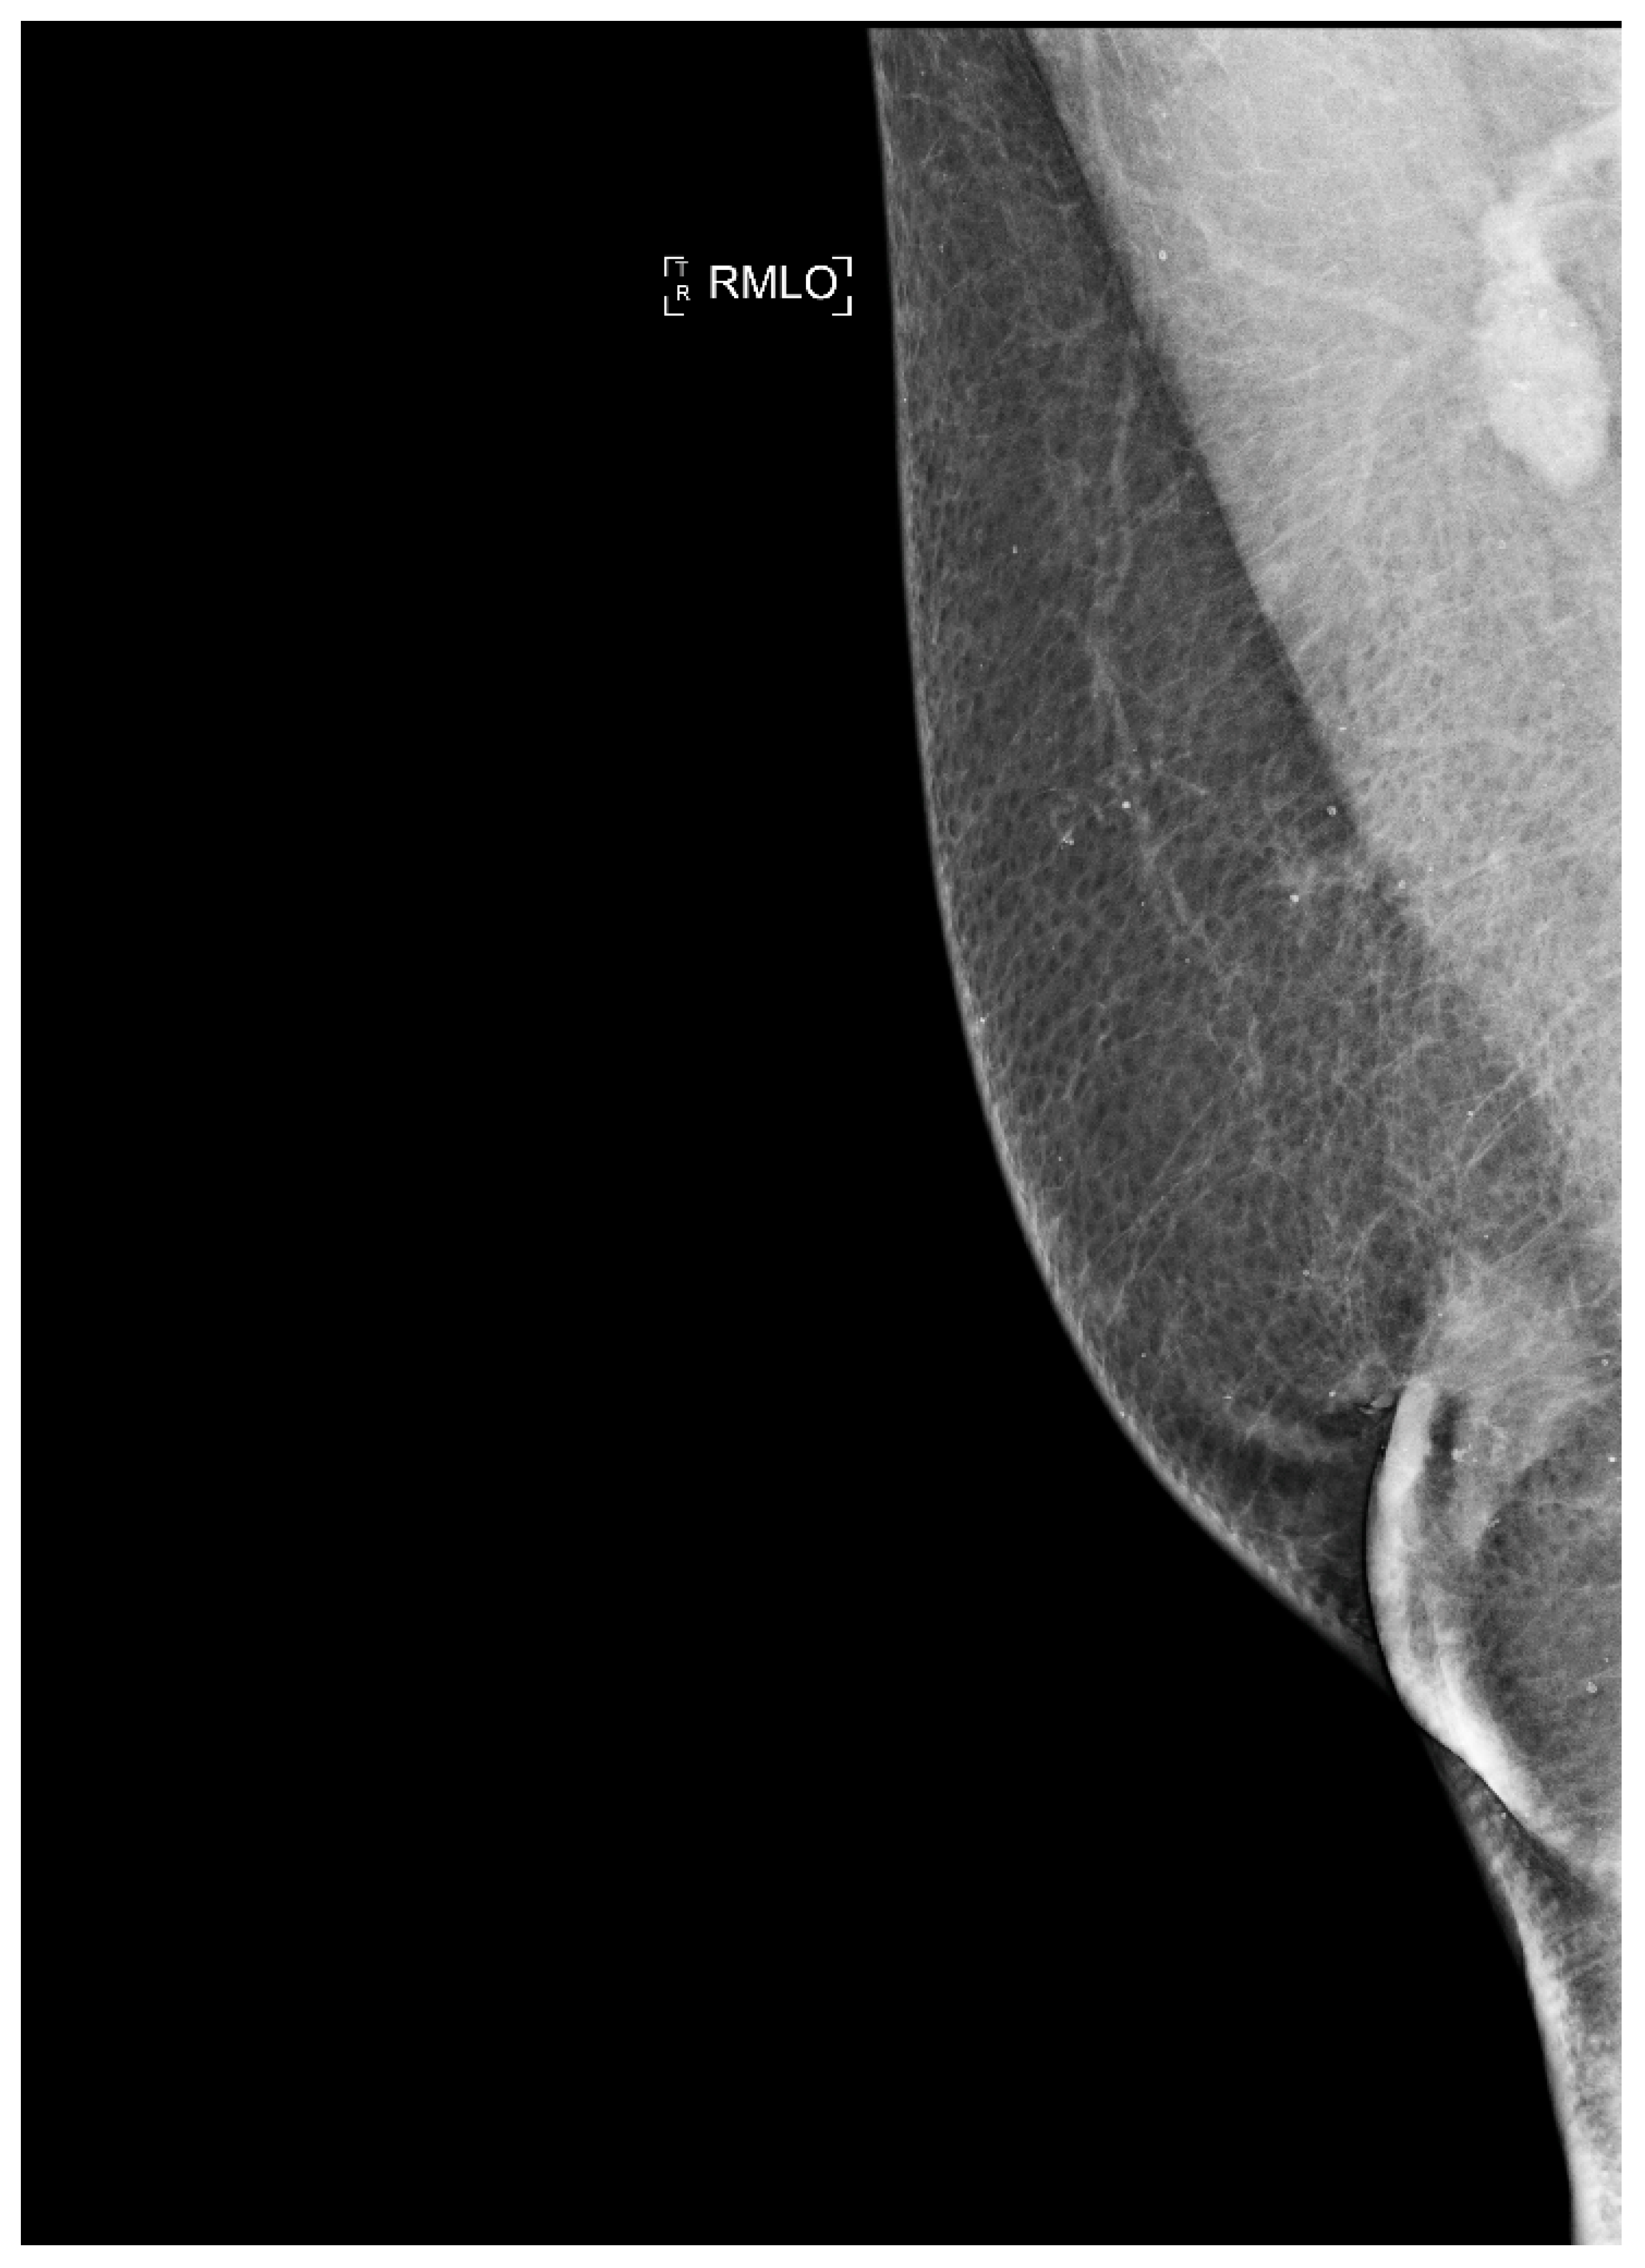

Figure 8.

Man with retroareolar tumor and skin thickening.